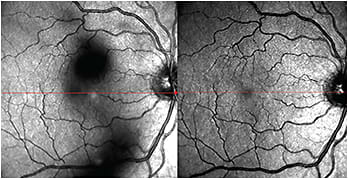

The entopic sensation of floaters (Figure), the gray patches that may temporarily obscure vision, can affect perceived quality of life in some individuals. Vitreous collagen reorganization and liquefaction (which occur in all individuals over time) results in aggregation of collagen fibrils, liquefaction of the gel (vitreous synchysis), and collapse (vitreous syneresis) of vitreous “away” from the retina (posterior vitreous detachment).1

Figure. Scanning laser ophthalmoscope image (left) of focal floaters in the right eye. When these floaters enter the optical axis, degradation of contrast sensitivity occurs due to light scattering. Postoperative SLO (right) demonstrates clearing of floaters after minimally invasive vitrectomy.